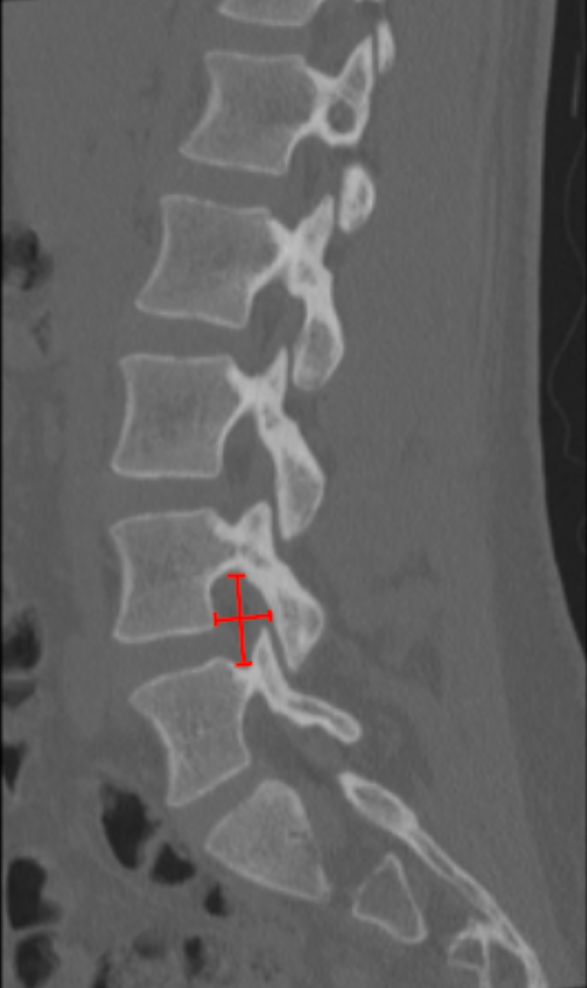

Lumbar foraminal height and width quantify the osseous dimensions of the neural foramen through which the exiting nerve root travels. Reduction in either parameter results in foraminal stenosis, a frequent cause of lumbar radiculopathy, most commonly due to disc height loss, osteophytes, facet hypertrophy, or spondylolisthesis.

CT is particularly useful for evaluating bony contributors to foraminal narrowing.

• Identify the lumbar level of interest on sagittal reconstruction.

• Select the true parasagittal slice that best profiles the neural foramen.

• Measure Foraminal Height:

• Identify the inferior cortex of the pedicle above and the superior cortex of the pedicle below.

• Measure the vertical distance (mm) between these points.

• Measure Foraminal Width:

• Identify the posterior vertebral body/disc margin (anterior boundary) and the anterior surface of the superior articular facet (posterior boundary).

• Measure the anteroposterior distance (mm).